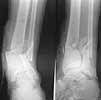

Male 22 yrs of age, RTA, front seat passenger in a truck. Sustained grade IIIB fracture of Tibia, and a Posterior dislocation of the Ipsilateral Left Hip.

Emergent closed reduction performed, and Tibial wound debrided. Next day Exfix applied and fibula plated. Initially femoral head fracture was not appreciated and it was thought that this is a posterior wall fracture. Presently two weeks down the line, Tibial wound is better but not completely healthy. and plastics want to wait for another five days, before they flap it. I enclose radiographs, Judet view, Ct scans in this and following mails.